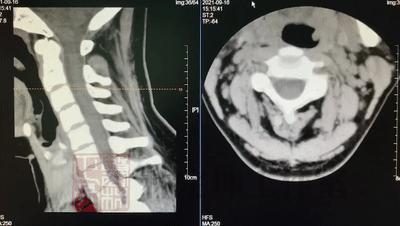

03 CT检查

在颈椎病的诊疗当中,CT检查利用X射线对颈部进行断层扫描,从而获得颈部的断面或者立体图像。如果说X光片是给颈部照了一张平面影像,那么CT检查则是在X光片的基础上 给颈部拍了一张三维的影像 ,能够 更加清晰地显示颈部结构,病变位置也能够更为清楚地被看到 。

可得信息:

(1)CT检查在X光片检查的基础上更能明确病变的范围、椎体及附件的情况;

(2)CT检查能够更为清楚地显示骨刺、韧带钙化等骨性病变;

(3)CT是诊断及定位椎管狭窄的较准确的方法,能显示椎管内受压迫的程度。